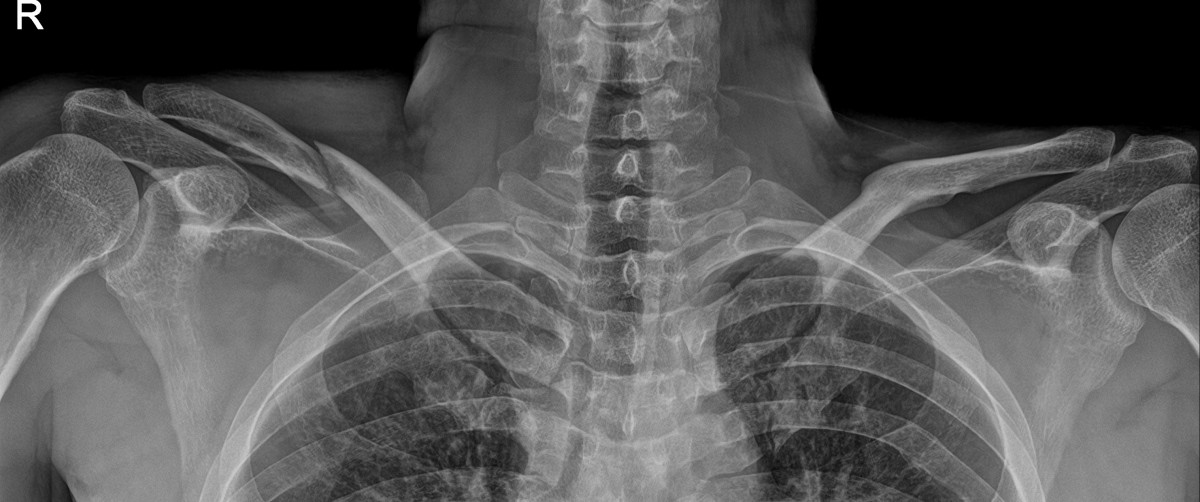

이재상원장님 어깨 골절 수술 박근O 환자

작성자 최고관리자 댓글 0건 조회 821회 작성일 25-09-16 14:54

dae765e4d9ac96aee867c9d6292d8784_1758002073_2826.jpg